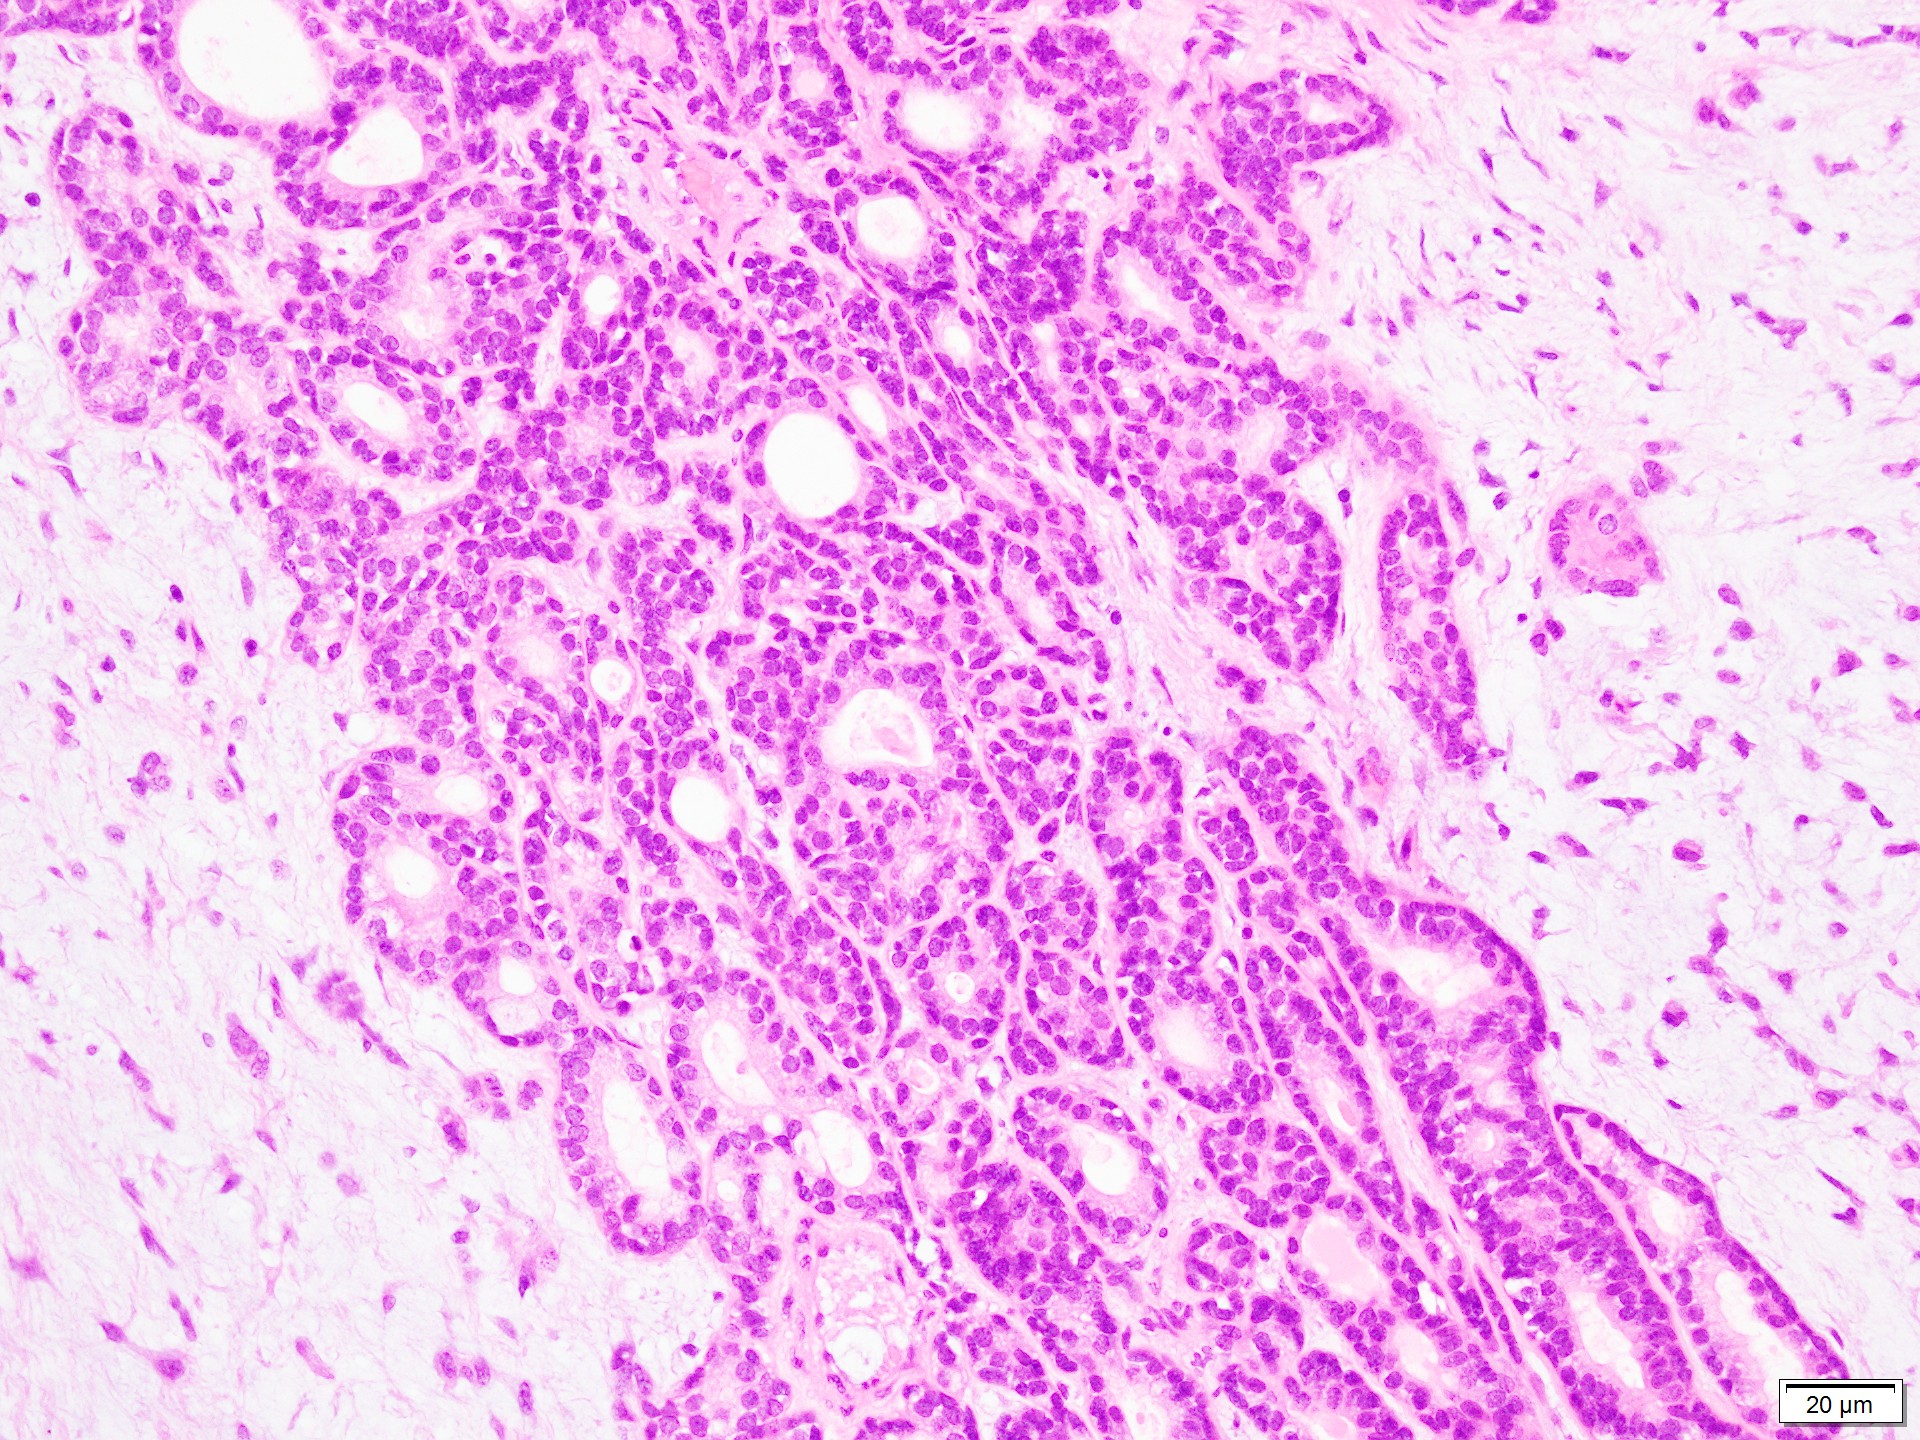

Giemsa染色で異染性を示す間質粘液と、円形〜紡錘形の筋上皮細胞、円〜類円形の核で均一な大きさの結合性良好な上皮細胞集塊がみられる。

組織標本では、豊富な粘液腫状基質に、星芒状・短紡錘形の筋上皮細胞成分と、管状を示す腺管上皮成分を認める。

腫瘍辺縁には圧排され菲薄化した唾液腺被膜・小葉間結合織を認める。悪性を疑う像は明らかではない。